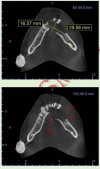

Destructive lesions in the craniofacial region especially in the jawbones, if associated with giant cells, include a spectrum of lesions that pose difficulty in diagnosis. The nature of such a lesion in the jawbones is questionable about whether it is a reactive/benign lesion or aggressive/non-aggressive. Clinical, radiological and histopathological correlation may be a reliable indicator to differentiate between the qualities of the lesion, which directly accounts for effective and individual planning of the treatment. Here we present a case of a woman in her late 20s with an unusual destructive lesion of the mandible.